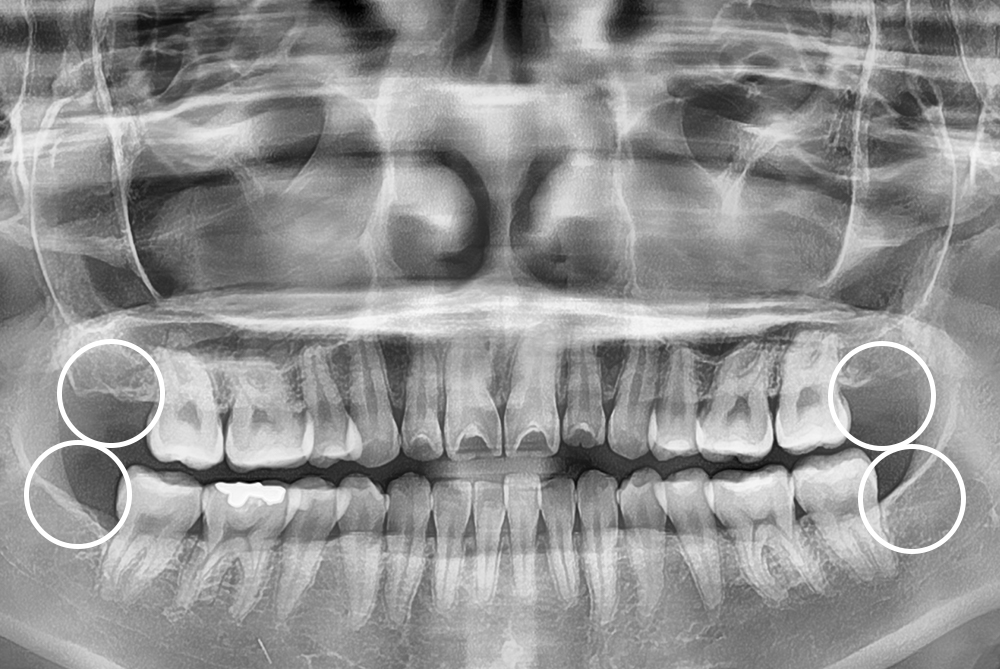

[사랑니] 매복 사랑니 발치

치료전 : 2016-07-05